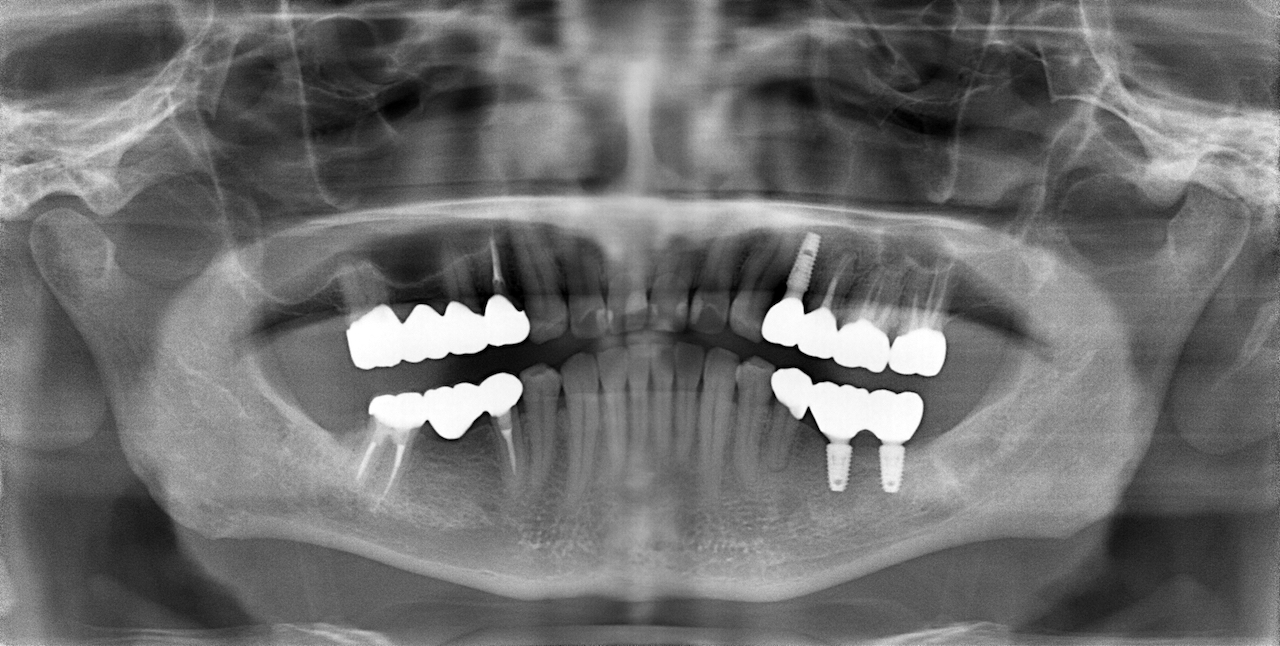

この患者さんは50代の男性で、若い時から様々な歯科治療をなさり、それに伴って抜歯をされたり、咬めなくなったそうです。そのなかで徐々に咬む位置がが分からなくなってきたとい言うお悩みで名取歯科医院にご来院されました。

顎関節の精密検査を行うと顎の状態も左右で異なり、咬み合わせもズレが大きくなったことで歯が欠けるなど、不調の理由がわかりました。

顎関節の軟骨(関節円板)がずれ、それに伴って咬み合わせが変化しても当時の歯科医師が適切な咬み合わせ(咬合調整)しなかったため、そのストレスが長年にわたり顎関節に影響し、痛みを生じてきたと検査から考えられました。

精密検査の中で「T-scan」という咬み合わせの専用の機械を使って診断すると、奥歯以外ではしっかり咬む箇所がなく、明らかに咬み合わせのバランスが良くありません。